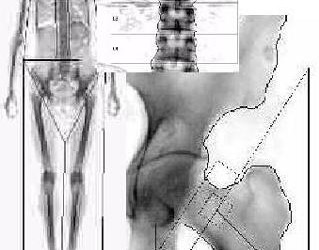

Densitatea minerală osoasă este un parametru cantitativ al compoziției osului, care are o dinamică dependentă de vârstă: crește din copilărie până la vârsta de 25-30 ani (când este maximă), apoi parcurge un platou până la 45-50 ani, după care începe să scadă cu 0.5-1%/an (pierdere legată de vârstă). Declinul  DMO este mai accentuat în postmenopauză, când datorită prăbușirii nivelului de estrogeni scade brusc mineralizarea oaselor și apare o scădere de circa 1-2% pe an. Principalul criteriu folosit în definirea osteoporozei este densitatea minerală osoasă (DMO, g/cm2) măsurată prin DXA (dublă absorbțiometrie cu raze X). Pentru a evalua gradul de mineralizare osoasă se folosesc 2 scoruri:  scorul T – reprezintă comparația între DMO a pacientului și DMO ideală (media tinerilor de 25-30 ani, când capitalul osos este maxim) și exprimată în deviație standard, scorul Z  - care compară DMO a pacientului examinat cu DMO medie a vârstei. Diagnosticul de osteoporoză se pune la un pacient cu scor T mai mic de – 2.5 DS sau la un pacient cu scor T mai mare de – 2.5 DS dar care prezintă o fractură de fragilitate (definită ca o fractură apărută la căderea din picioare sau sub acțiunea unei forțe care în mod normal nu ar trebui să determine fracturarea osului). Utilitatea DXA este reprezentată de faptul că poate diagnostica osteoporoza înainte de producerea unei fracturi de fragilitate. Accesibilitatea DXA și introducerea ei în criteriile de diagnostic ale osteoporozei a făcut ca examenul radiologic convențional (radiografie de șold sau de coloană lombară) să treacă pe plan secund. Trebuie reținut și faptul că nu orice pacient cu scor T sub – 2.5 DS are osteoporoză (cum sunt spre exemplu pacienții cu osteomalacie, afecțiune apărută la adult datorită deficitului de vitamină D).